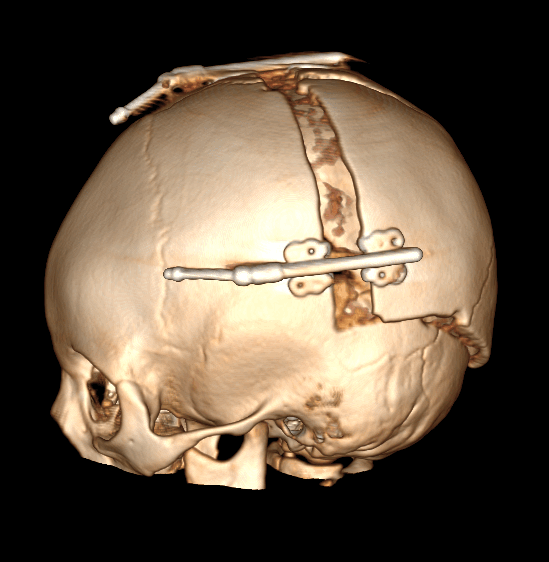

Деформация черепа, вызванная преждевременным односторонним слиянием (стенозом) коронарного шва – Плагиоцефалия.

Плагиоцефалия (от греч. Рlagio – косой + kephale – голова) – косая асимметрия черепа. Может быть лобной и затылочной.

Синостозна лобная плагиоцефалия или гемикоронарный синостоз (ГКС) – связан с односторонним стенозов коронарного шва, который привод к заращению лобно-клиновидного и лобно-решетчатого швов на той же стороне. Всегда сопровождается деформацией костей лицевого скелета.

Рис. №5 Плагиоцефалия

а), б) - СКТ снимки плагиоцефалии

в), г) - схема хирургического лечения. Выдвижение вперед асимметричной части черепа и ее фиксация – фронто-орбитальная реконструкция.